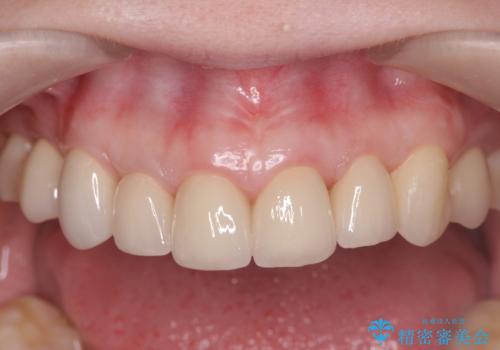

丁寧な虫歯の除去・歯周組織の整備、適合の良い精密なセラミッククラウンの製作といった丁寧な治療の積み重ねが良好な治療結果を得ることにつながります。